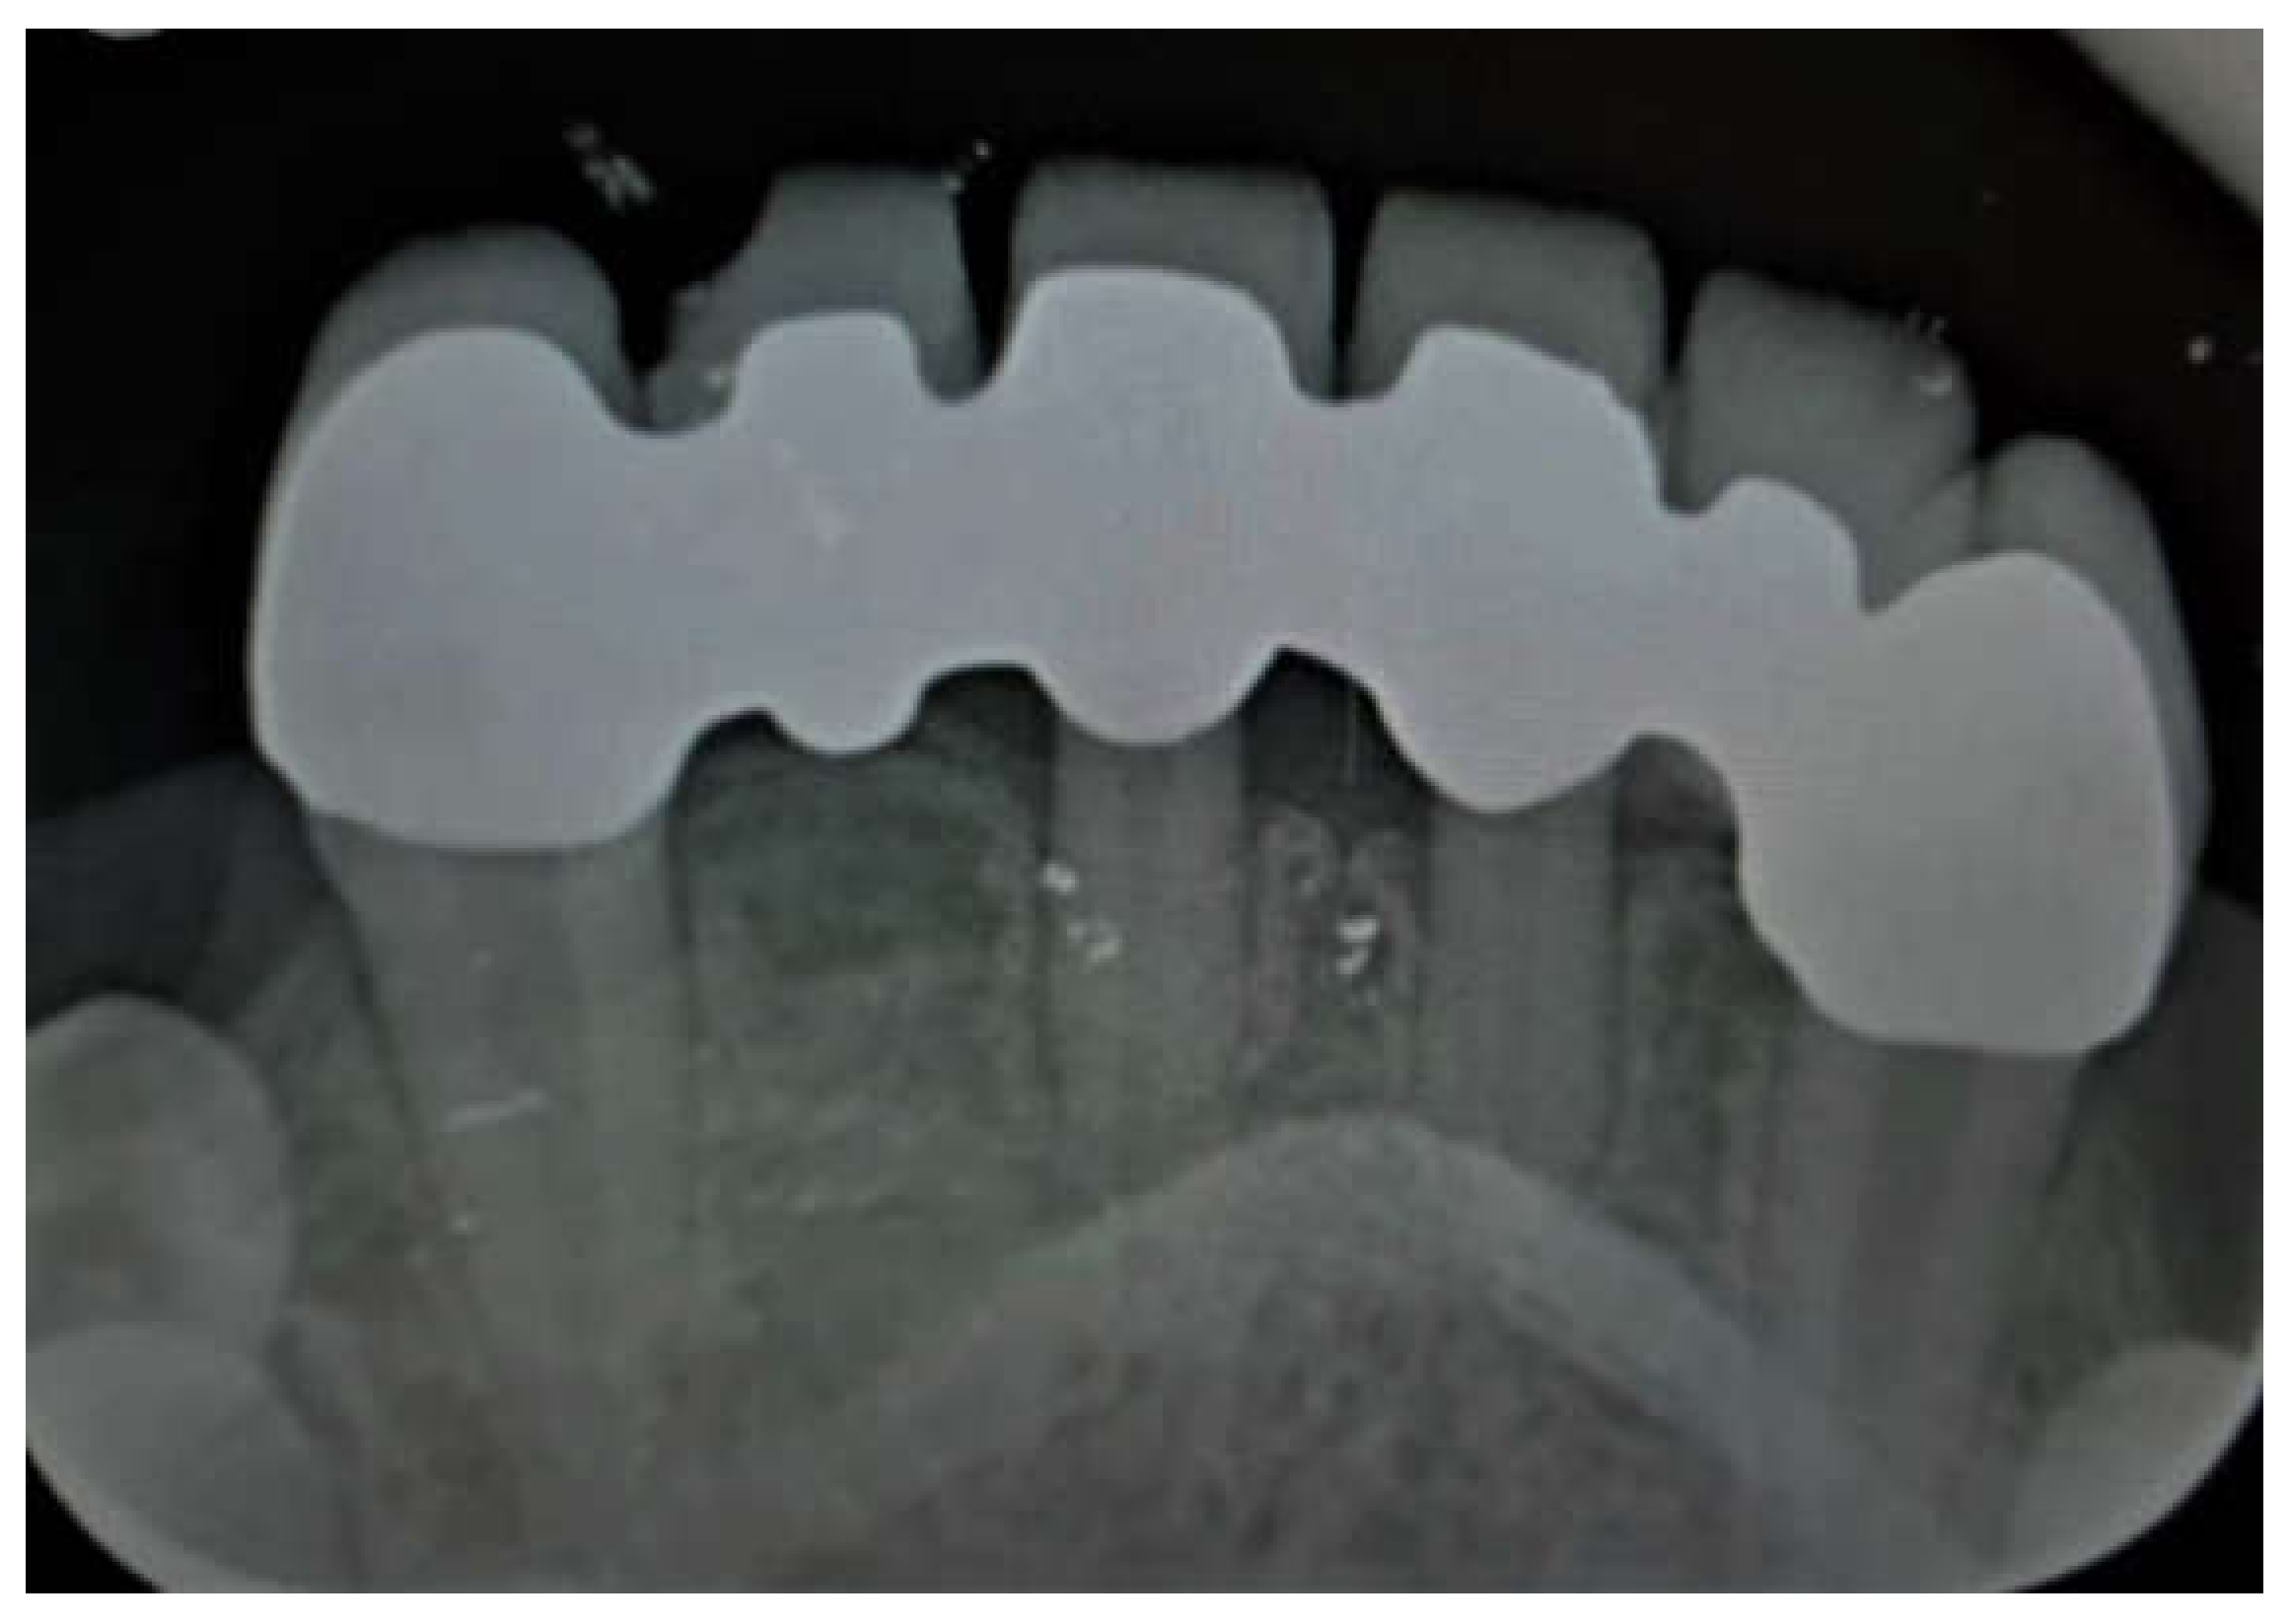

Primary Teeth Supported Fixed Prosthesis—A Predictable Treatment Alternative

2. Materials and Methods

3. Results